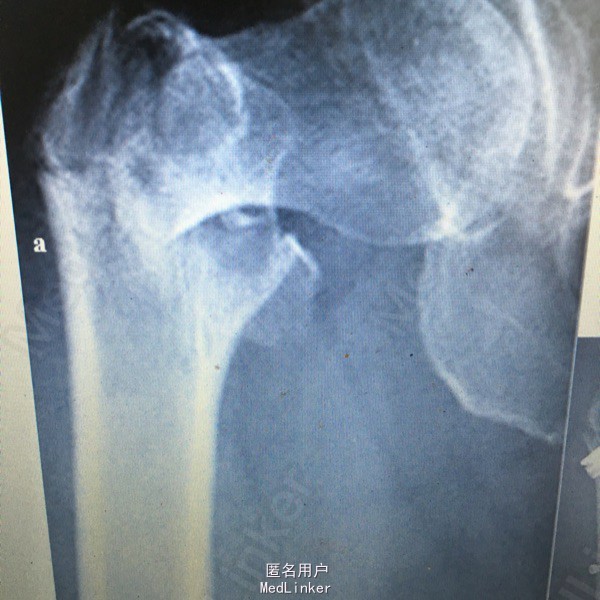

女性79岁,摔伤致右侧股骨粗隆间骨折

无合并伤,入院后3天手术

右侧股骨粗隆间骨折。 女患,79岁,a.术前X光片示股骨粗隆间骨折;b.术后X光片示骨折复位满意,内固定位置佳;c.术后12个月示骨折愈合良好